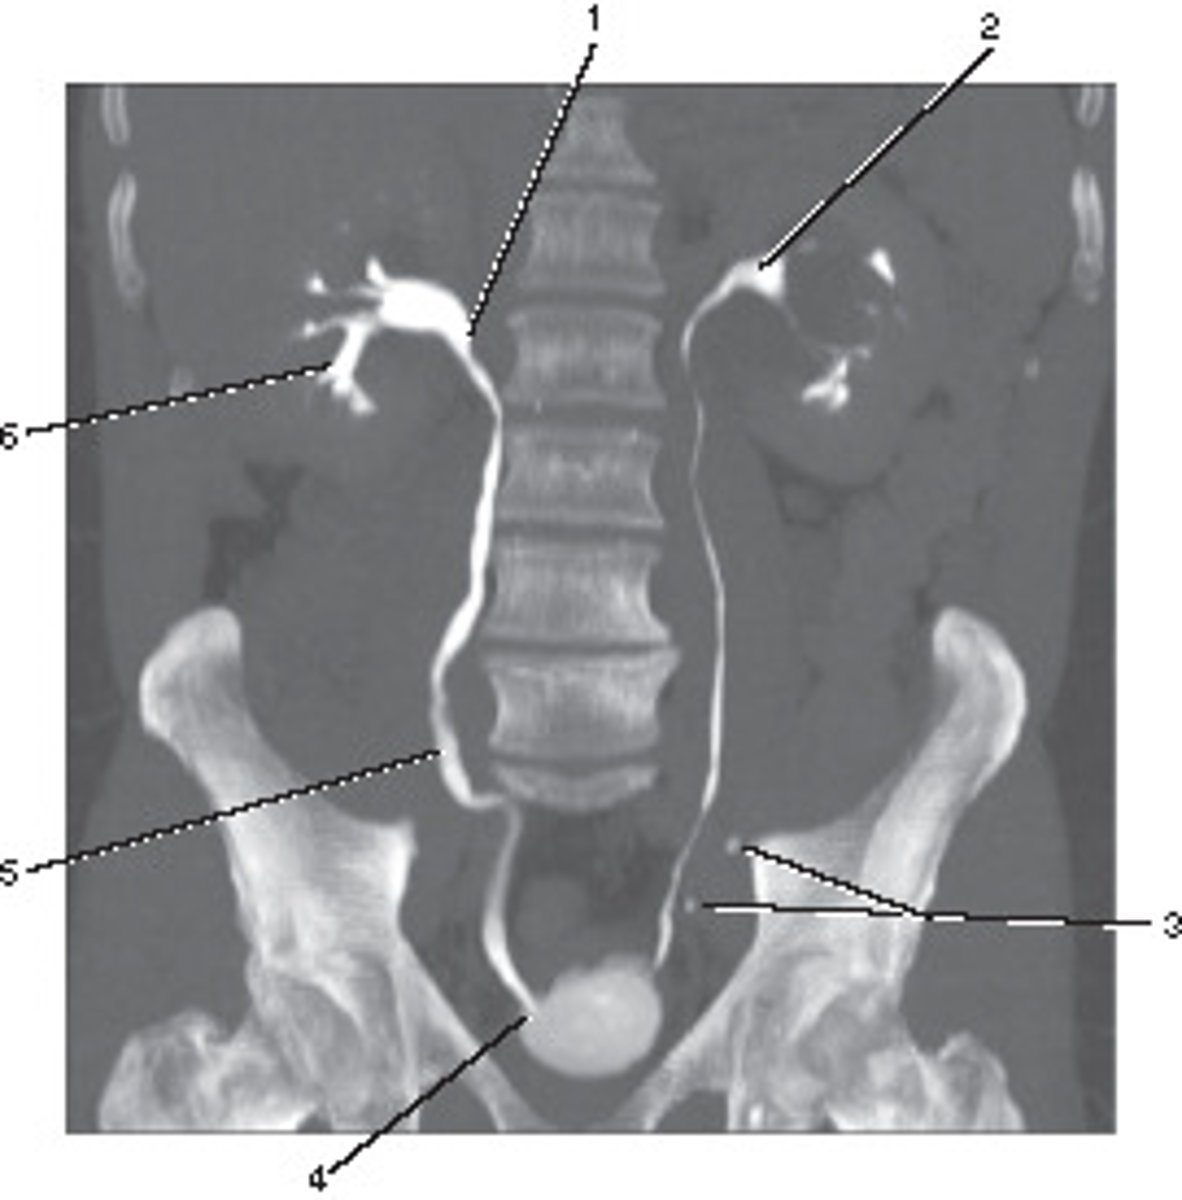

Ureter

Number 8 corresponds to which of the following?

<p>Number 8 corresponds to which of the following?</p>

Ureterovesical Junction (UVJ)

Number 4 corresponds to which of the following?

<p>Number 4 corresponds to which of the following?</p>